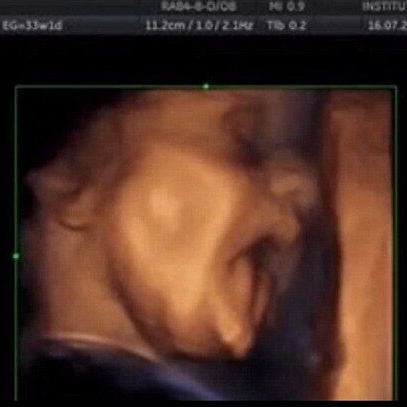

驚き! 胎児が子宮の中で歌をうたう映像を公開

驚き! 胎児が子宮の中で歌をうたう映像を公開。 イギリスの『デイリー・メール』によると、胎児は16週になると音が聞こえることが研究でわかった…